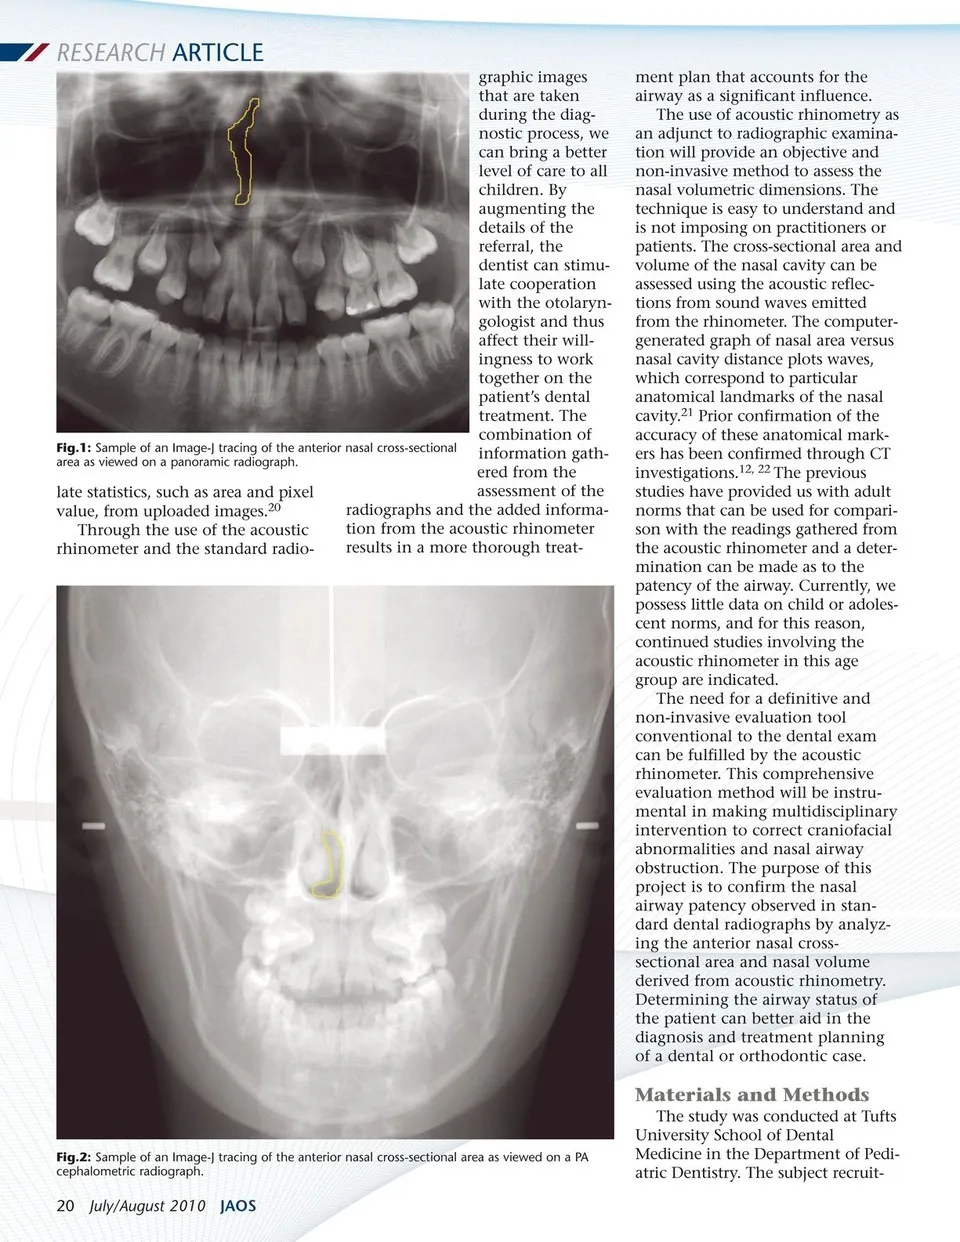

RESEARCH ARTICLE graphic images that are taken during the diag-nostic process, we can bring a better level of care to all children. By augmenting the details of the referral, the Fig.1: Sample of an Image-J tracing of the anterior nasal cross-sectional area as viewed on a panoramic radiograph. late statistics, such as area and pixel value, from uploaded images.20 Through the use of the acoustic rhinometer and the standard radio-dentist can stimu-late cooperation with the otolaryn-gologist and thus affect their will-ingness to work together on the patient’s dental treatment. The combination of information gath-ered from the assessment of the radiographs and the added informa-tion from the acoustic rhinometer results in a more thorough treat-ment plan that accounts for the airway as a significant influence. The use of acoustic rhinometry as an adjunct to radiographic examina-tion will provide an objective and non-invasive method to assess the nasal volumetric dimensions. The technique is easy to understand and is not imposing on practitioners or patients. The cross-sectional area and volume of the nasal cavity can be assessed using the acoustic reflec-tions from sound waves emitted from the rhinometer. The computer-generated graph of nasal area versus nasal cavity distance plots waves, which correspond to particular anatomical landmarks of the nasal cavity.21 Prior confirmation of the accuracy of these anatomical mark-ers has been confirmed through CT investigations.12, 22 The previous studies have provided us with adult norms that can be used for compari-son with the readings gathered from the acoustic rhinometer and a deter-mination can be made as to the patency of the airway. Currently, we possess little data on child or adoles-cent norms, and for this reason, continued studies involving the acoustic rhinometer in this age group are indicated. The need for a definitive and non-invasive evaluation tool conventional to the dental exam can be fulfilled by the acoustic rhinometer. This comprehensive evaluation method will be instru-mental in making multidisciplinary intervention to correct craniofacial abnormalities and nasal airway obstruction. The purpose of this project is to confirm the nasal airway patency observed in stan-dard dental radiographs by analyz-ing the anterior nasal cross-sectional area and nasal volume derived from acoustic rhinometry. Determining the airway status of the patient can better aid in the diagnosis and treatment planning of a dental or orthodontic case. Fig.2: Sample of an Image-J tracing of the anterior nasal cross-sectional area as viewed on a PA cephalometric radiograph. 20 July/August 2010 JAOS Materials and Methods The study was conducted at Tufts University School of Dental Medicine in the Department of Pedi-atric Dentistry. The subject recruit-